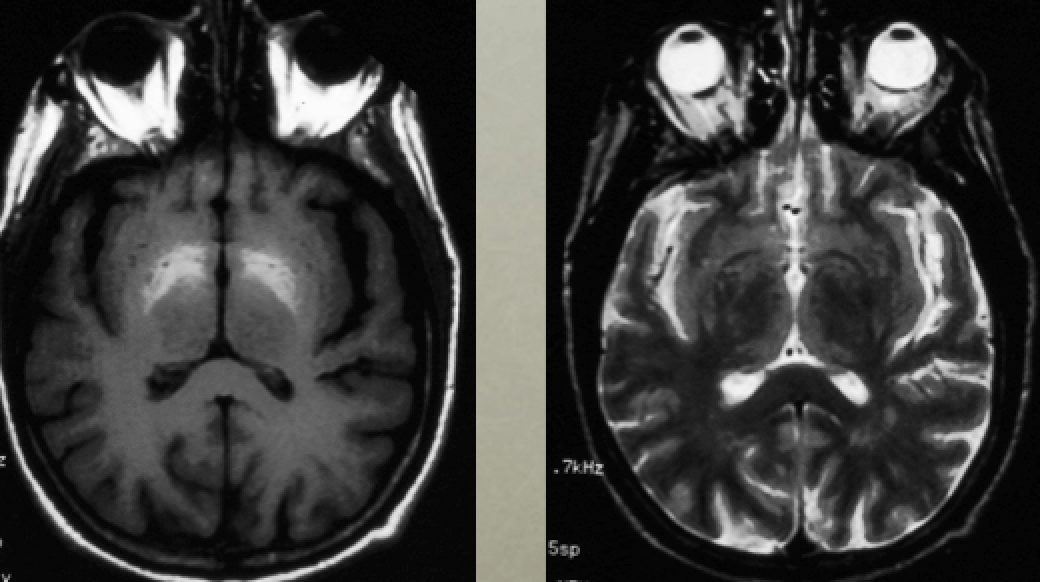

Elderly woman develops chorea during a prolonged hospitalization for bowel resection

Diagnosis?

Why does this condition result in this MRI signal pattern?

Other conditions that can have this?

TPN-related manganese toxicity

Manganese is bright on T1, normal to dark on T2

Wilson’s disease (copper) can sometimes have T1 bright putamen (sometimes globus pallidus), too, but will be definitely be T2 bright. “Face of giant panda” in midbrain

PKAN/NBIA (iron): T1 slightly bright, T2 dark globus pallidi; can see iron on SWI imaging; “Eye of the tiger”

Basal ganglia calcifications are also T1 bright (TORCH infections, Toxo, Fahr disease, etc)

Hemorrhage can be T1 bright (for example, CO poisoning could cause hemorrhage)

(thanks to Raf Llinas)